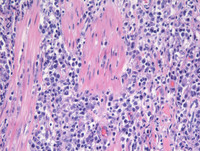

Figure 3: H&E High Power in Plasmacytoma-Like PTLD, EBV+

These higher power images depict the infiltrate percolating and destroying the muscularis propria.

The high magnification on the right side shows classic plasmacytic cytomorphology. Note that the neoplastic cells do not exhibit morphology compatible with centroblasts (as in DLBCL) or plasmablasts (plasmablastic lymphoma), both of which may also be EBV positive.